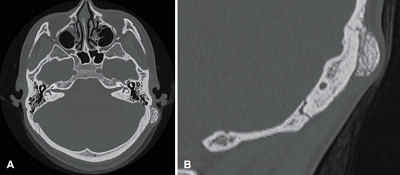

476 영상유도수술 시스템을 이용한 협골궁 골절 수술의 임상적 경험: 단일 기관 25예 분석

양승혁, 정한진

Korean J Otorhinolaryngol-Head Neck Surg. 2025;68(11):476-480.   Published online September 30, 2025

DOI: https://doi.org/10.3342/kjorl-hns.2025.00248

kjorl-hns-2025-00248f1.jpgkjorl-hns-2025-00248f2.jpgkjorl-hns-2025-00248f3.jpg